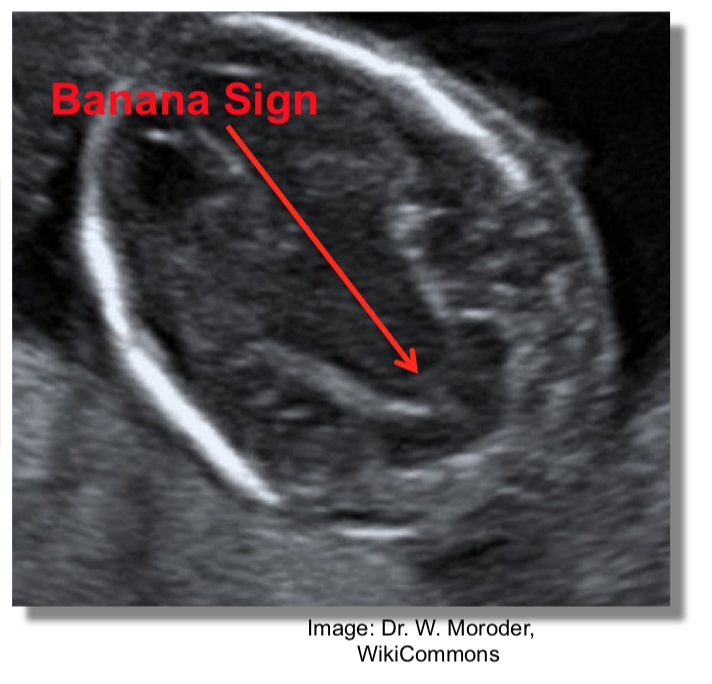

(compression of the cerebellum in posterior fossa)